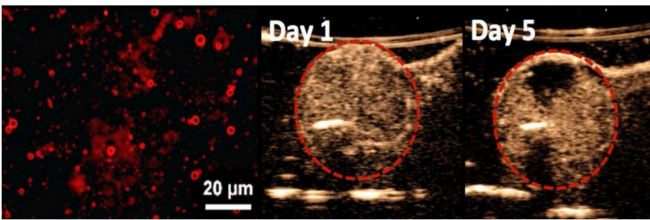

Deliver 产品主要是在Prime上负载临床上化疗用药doxorubicin(DOX)的载药微气泡,使微气泡除了可作为超声造影剂以外,同时可达到超声波驱动的药物释放和治疗肿瘤的目的。Deliver最大优势在于注入活体内后,能先利用微气泡的显影功能在超声波影像上呈现肿瘤的位置,接着通过在目标位置加强超声波可驱动Deliver内药物在靶向部位大量释放,达到肿瘤局部化疗的功效。图10显示骨肉瘤上利用Deliver的治疗结果:,在治疗后第五天可以利用超声波显影剂观察到肿瘤出现坏死(necrosis)。

图10左图为Deliver的荧光显微镜图像;右图为利用超声波驱动Deliver释放DOX进行治疗,可以观察到在治疗后第五天肿瘤内部出现坏死

Figure 10 Left:Fluorescence microscopy image of deliver; Right: Tumor necrosis on day 5 after injection of Deliver.